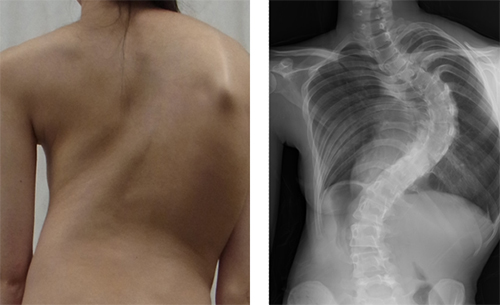

側彎とは、背骨が横に曲がった状態を言います(図1)。ヒトの背骨は完全に真っ直ぐではありませんが、曲がりの角度が10度以上になると病的(側彎症)と考えられています。曲がりの角度が20度を超えると、装具の着用など何らかの治療をする必要が生じ、40度を超えると、多くの場合手術治療が必要となります。さらに重度になった場合は、肺機能が低下し、腰痛や背部痛の発症が増加するとされています。進行すると治療が困難になるので、早期発見が大切です。

図1 側彎症の外観とX線画像

左:側彎症患者の外観。右:脊椎X線画像(背面図)。背骨が大きく弯曲していることが分かる。